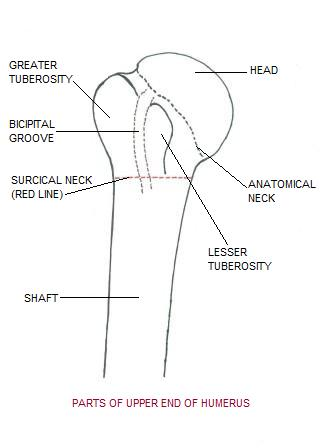

Proximal Humerus Fractures Trauma Orthobullets

Proximal Humerus Fractures Trauma Orthobullets

Proximal Humerus Approach Anterolateral Approach

Proximal Humerus Approach Anterolateral Approach